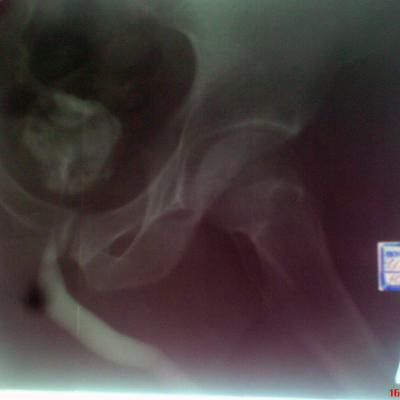

Возможно у Вас проконсультироваться таким образом,я вышлю Вам снимки уретрограмм а Вы скажете свое мнение.